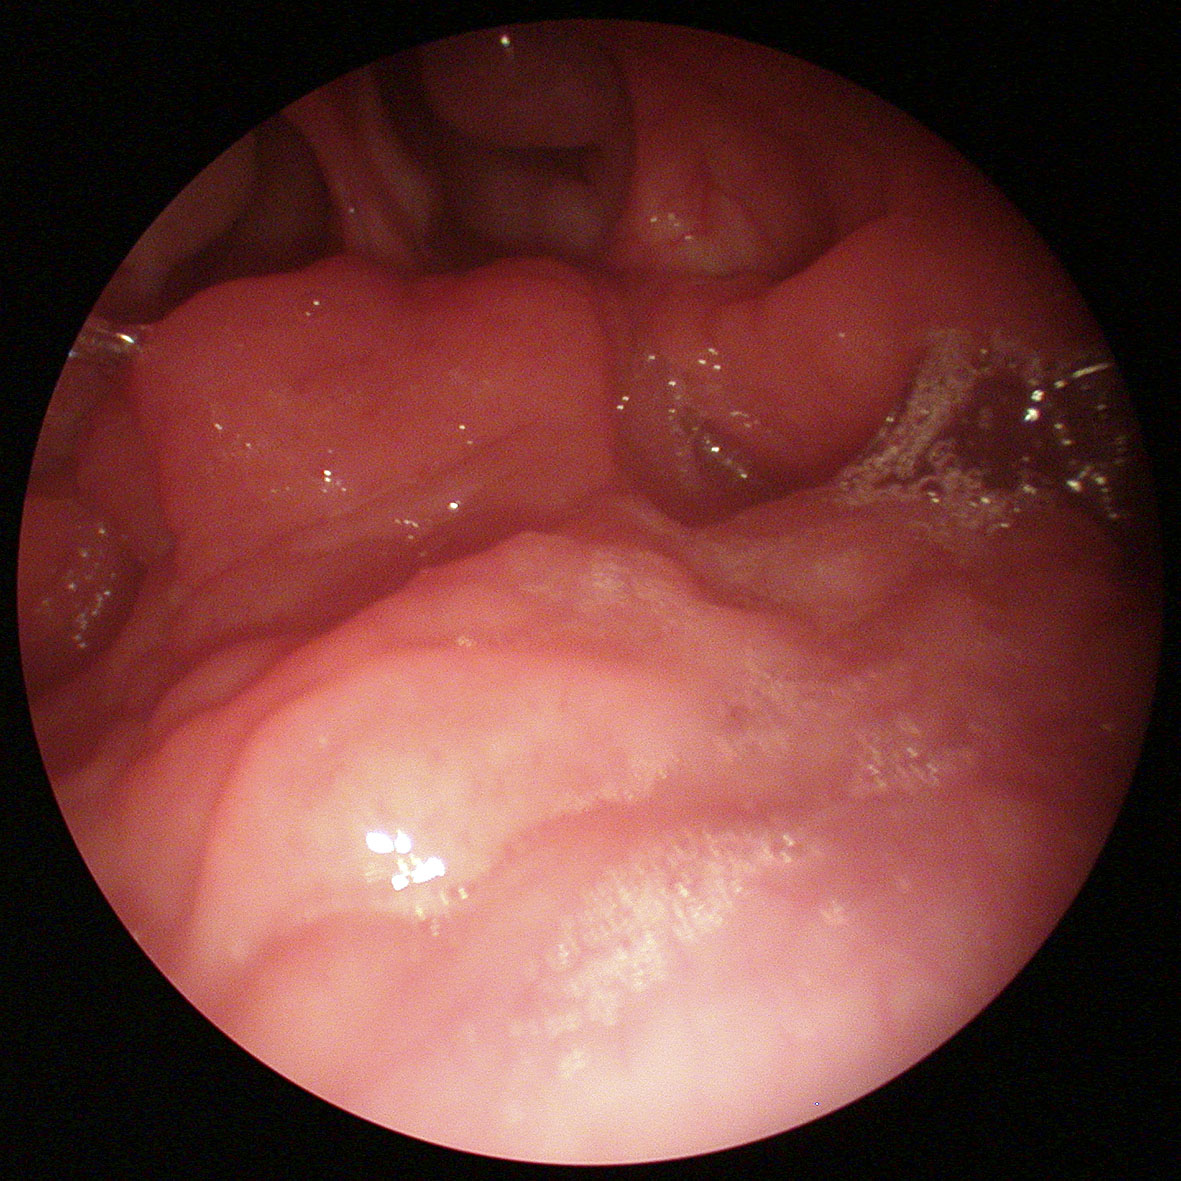

Es gibt viele Ursachen für Druckausgleichsprobleme beim Tauchen. Chronische Nasennebenhöhlenentzündungen, anatomische Besonderheiten, Vernarbungen im Nasenrachen, gut- und sehr selten bösartige Tumoren im Nasenrachen und manchen mehr, dass durch eine endoskopische Untersuchung durch den HNO-Arzt ausgeschlossen werden sollte. Findet sich keine Ursache, die anderweitig behoben werden kann, empfehlen wir die obengenannten Maßnahmen und unterstützen die Behandlung einer möglichen chronischen Entzündung der Schleimhaut durch örtlich wirkende Kortison Nasensprays.

Es gibt eine Vielzahl von operativen Behandlungen, die bei Tubenbelüftungsstörungen angewandt wurden. Tubenendoskopie, Tubenlaserverfahren, Golddraht Einlegen, Tubensprengung und vieles mehr. Keines dieser Verfahren hat sich bisher durchsetzen können. Seit kurzem gibt es ein sehr vielversprechendes Verfahren, dass wir im Rahmen einer wissenschaftlichen Untersuchung im DIAKO in Bremen getestet haben. Hierzu wurde dem Patienten (diese Methode wird auch bei Nichttauchern angewandt) in Narkose ein Instrument in die Nase eingeführt.

Über dieses Instrument wird ein Katheter in die Ohrtrompete der betroffenen Seite oder auch beider Seiten eingeführt. Der Katheter funktioniert ähnlich einem Katheter den man aus der Herzkranzgefäß-Dilatation kennt, der so genannte „Herzkatheter“. Der Katheter, der speziell für die Ohrtrompete emtwickelt wurde, wird in die Ohrtrompete eingeführt und dort für zwei Minuten auf 10 bar mittels Kochsalzlösung aufgepumpt.